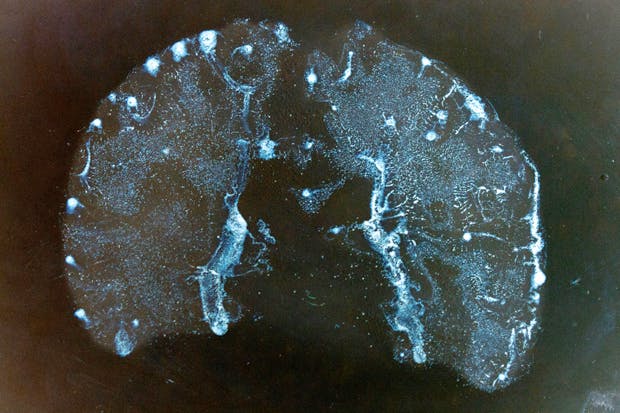

The curators have placed the centrepiece of their latest exhibition, Susan Aldworth’s lithographs, including ‘Passing Thoughts 13’ (above), on the wall of the partition facing the walkway. Whether or not this decision was intentional or forced, it was inspired. The blurb says that the lithographs ‘reflect on the general condition of schizophrenia’, and it’s not lying. To contemplate these images, while purposeful strangers stride about you to a disjointed background soundtrack of clunking doors and invisible voices, is deeply unsettling. The Blyth Gallery would make a poor show of John Constable; but it’s perfect for Aldworth’s meditations on consciousness, psychosis and the physical brain. Until 1 May.